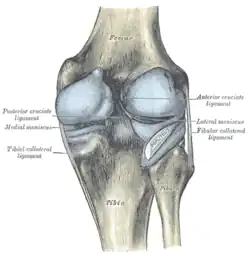

Die Kreuzbänder (Ligamenta cruciata) ziehen von der Grube zwischen den Oberschenkelknorren zum Schienbein. Von der Seite und von vorn betrachtet überkreuzen sie sich dabei in ihrem Verlauf.

Indem die Kreuzbänder ein verschobenes Abgleiten der Gelenkflächen nach vorn oder hinten (Translation) verhindern, stabilisieren sie das Knie. Zusätzlich hemmen sie die Drehbewegung, vor allem die Einwärtsdrehung, bei der sie sich umeinander wickeln und das vordere Kreuzband sich spannt. Bei der Auswärtsdrehung wickeln sie sich auseinander, wodurch das Knie bei maximaler Streckung immer ein wenig nach außen gedreht wird (Schlussrotation). Die klassische Verletzung des vorderen Kreuzbandes tritt daher, z. B. beim Skifahren, bei gebeugtem Knie und Einwärtsdrehung unter Gewalteinwirkung auf.

Vorderes Kreuzband

Das vordere Kreuzband (Ligamentum cruciatum anterius – bei Tieren Ligamentum cruciatum craniale) zieht von der vorderen Einmuldung zwischen den Schienbeinknorren zur Seite und etwas nach hinten, um an der Innenseite des seitlichen Oberschenkelknochens anzusetzen. Dabei teilt es sich in ein vorne-mittiges und in ein hinten-seitliches Bündel auf. Durch die weite Fächerung der Ursprungsfläche dieser Bündel ist sowohl bei Beugung, als auch bei Streckung ein Teil des vorderen Kreuzbandes gespannt. Dadurch verhindert es bei ausgestrecktem Bein eine Überstreckung (Hyperextension), während es bei Beugung dem Vorschub des Schienbeines entgegenwirkt („vordere Schublade“).

Hinteres Kreuzband

Das hintere Kreuzband (Ligamentum cruciatum posterius – bei Tieren Ligamentum cruciatum caudale) ist kräftiger und hat seinen Ursprung in der hinteren Einmuldung des Schienbeinplateaus und zieht nach vorne-mittig, um an der seitlichen Vorderfläche des inneren Oberschenkelknochens anzusetzen. Es spannt sich bei Beugung und verhindert damit ein nach hinten gerichtetes Weggleiten des Schienbeines (hintere Schublade). Bei ausgestrecktem Bein unterstützt das hintere Kreuzband das vordere beim Vorbeugen einer Überstreckung. Seine Hauptaufgabe ist jedoch die Stabilisierung des Knies bei Beugung und unter Last.

Menisken

Da die miteinander in Verbindung stehenden (artikulierenden) Gelenkflächen nicht genau aufeinander passen, wird diese „Ungleichheit“ (Inkongruenz) durch halbmondförmige Faserknorpelscheiben, die Menisken ausgeglichen, die den Drehbewegungen folgen können. Eine weitere Aufgabe der Menisken besteht in der Vergrößerung der Kontaktfläche zwischen Schienbein und Oberschenkelknochen.

Man unterscheidet einen Innenmeniskus (Meniscus medialis), der C-förmig, größer und etwas unbeweglicher (da mit dem Innenband verwachsen) ist, und einen Außenmeniskus (Meniscus lateralis), der kreisförmig, kleiner und beweglicher ist (da er mit keinem Seitenband verwachsen ist). Die Menisken sind im Querschnitt keilförmig. Die hohe Kante liegt außen, die niedrige innen. Da die Oberschenkelknochen genau in der Mitte direkt auf dem Schienbeinplateau und peripher auf den Menisken aufliegen, tragen diese einen wesentlichen Teil der Last.

Seitliche Bandsicherung

Das Knie hat zwei Seitenbänder: ein inneres (Ligamentum collaterale tibiale) und ein äußeres (Ligamentum collaterale fibulare). In Streckstellung sind beide Seitenbänder (auch Kollateralbänder genannt) gespannt und verhindern somit die Drehbewegung, in Beugestellung verkleinert sich der Krümmungsradius, Ursprung und Ansatz nähern sich einander an und die Bänder sind infolgedessen entspannt. Beide Seitenbänder stabilisieren das Kniegelenk in seitlicher Richtung (Frontalebene), damit ein Wegknicken in eine O-Bein-Stellung (Genu varum) oder X-Bein-Stellung (Genu valgum) verhindert wird.

Das Innenband (Ligamentum collaterale tibiale bzw. mediale) ist ein dreieckiges, flaches Band, das breitflächig vom Aufsatz des inneren Oberschenkelknochens (Epicondylus medialis femoris) zur Innenseite des Schienbeines (Facies medialis tibiae) verläuft. Es ist in die äußere Schicht der Gelenkkapsel eingebaut und mit dem Innenmeniskus verwachsen.

Das Außenband (Ligamentum collaterale fibulare bzw. laterale) ist ein kräftiges Band, das in seinem dorsalen Abschnitt zylinderförmig vom Aufsatz des seitlichen Oberschenkelknochens (Epicondylus lateralis femoris) zum Wadenbeinkopf (Caput fibulae) zieht. Es hat keine feste Verbindung zur Gelenkkapsel und den Menisken.